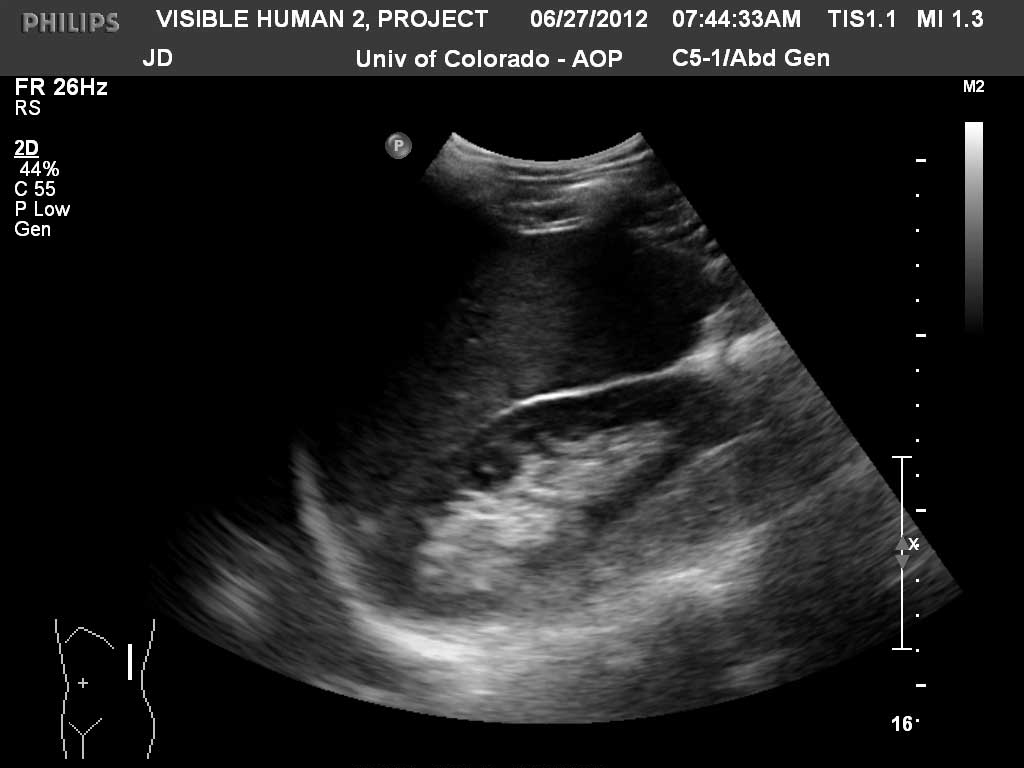

Long (Coronal) Left Kidney

Kidney

Renal Cortex

Renal Sinus Fat

Spleen